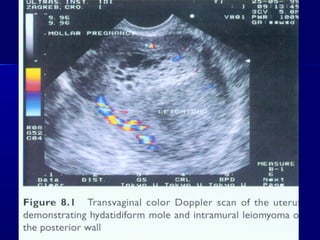

A sonographic findings of a molar pregnancy. The

characteristic “snowstorm” pattern is evident.

Transvaginal sonogram demonstrating the “ snow storm” appearance.